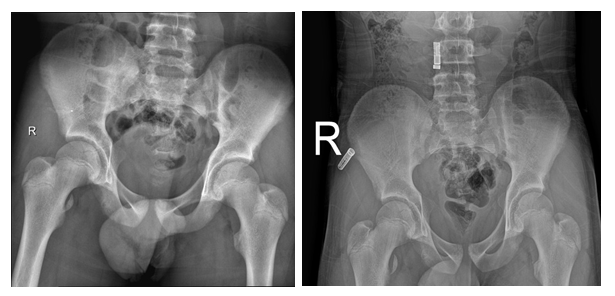

Figure 2X-ray taking for the pelvis in anterior-posterior view shows callus formation and complete healing of right lesser trochanter. (This x ray taking after 16 weeks of the time of injury).

We report a case of LTF where the patient underwent bed rest for 6 weeks with use of axillary crutches. Pain was managed by anti-inflammatory medication. After 6 weeks of injury, patient start progressive weight bearing period. After 12 weeks of the injury, the patient was walking and running without limitation nor pain. After 16 weeks from the time of injury the x-ray shows complete healing of the fracture with formation of good callus. The patient returned to non- contact sport by 16 weeks and to full sport activities by 20 weeks.